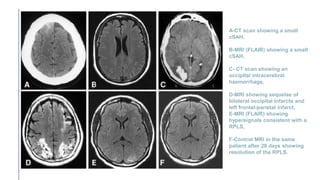

A-CT scan showing a small

cSAH,

B-MRI (FLAIR) showing a small

C- CT scan showing an

occipital intracerebral

haemorrhage,

D-MRI showing sequelae of

bilateral occipital infarcts and

left frontal-parietal infarct,

E-MRI (FLAIR) showing

hypersignals consistent with a

RPLS,

F-Control MRI in the same

patient after 28 days showing

resolution of the RPLS.

A-CT scan showinga small cSAH, B-MRI (FLAIR) showing a small cSAH, C- CT scan showing an occipital intracerebral haemorrhage, D-MRI showing sequelae of bilateral occipital infarcts and left frontal-parietal infarct, E-MRI (FLAIR) showing hypersignals consistent with a RPLS, F-Control MRI in the same patient after 28 days showing resolution of the RPLS.